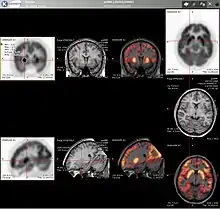

PET imaging with 18F-FDG takes advantage of the fact that the brain is normally a rapid user of glucose. Standard 18F-FDG PET of the brain measures regional glucose use and can be used in neuropathological diagnosis.

Brain pathologies such as Alzheimer's disease greatly decrease brain metabolism of both glucose and oxygen in tandem. Therefore 18F-FDG PET of the brain may also be used to successfully differentiate Alzheimer's disease from other dementing processes, and also to make early diagnoses of Alzheimer's disease. The advantage of 18F-FDG PET for these uses is its much wider availability. Some 18F based radioactive tracers used for Alzheimer's include florbetapir, flutemetamol, PiB and florbetaben, which are all used to detect amyloid-beta plaques (a potential biomarker for Alzheimer's) in the brain.[16]

PET imaging with FDG can also be used for localization of seizure focus. A seizure focus will appear as hypometabolic during an interictal scan.[17] Several radiotracers (i.e. radioligands) have been developed for PET that are ligands for specific neuroreceptor subtypes such as [11C] raclopride, [18F] fallypride and [18F] desmethoxyfallypride for dopamine D2/D3 receptors, [11C] McN 5652 and [11C] DASB for serotonin transporters, [18F] Mefway for serotonin 5HT1A receptors, [18F] Nifene for nicotinic acetylcholine receptors or enzyme substrates (e.g. 6-FDOPA for the AADC enzyme). These agents permit the visualization of neuroreceptor pools in the context of a plurality of neuropsychiatric and neurologic illnesses.